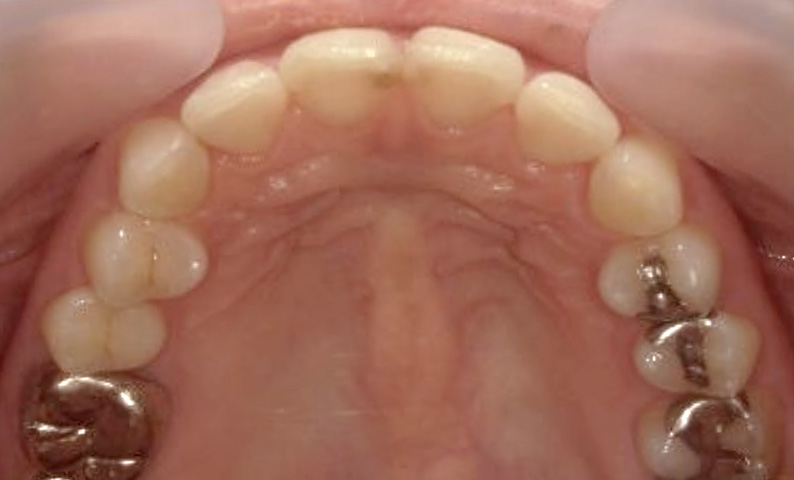

症例_025 上下顎の部分矯正

治療期間:13ヶ月金額:51万円+税女性前歯のガタガタ出っ歯

| Before | After |

|---|---|